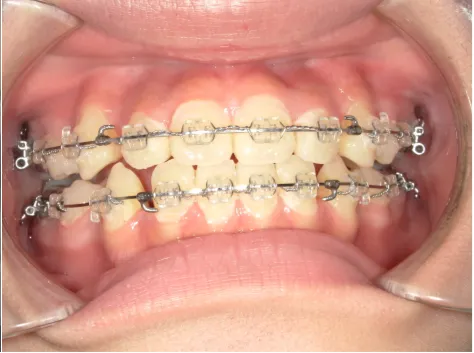

治療中⑧高1:15y11m 抜歯治療中

治療中⑨高2:17y1m 抜歯治療中

治療後⑩高2:17y7m 抜歯治療終了